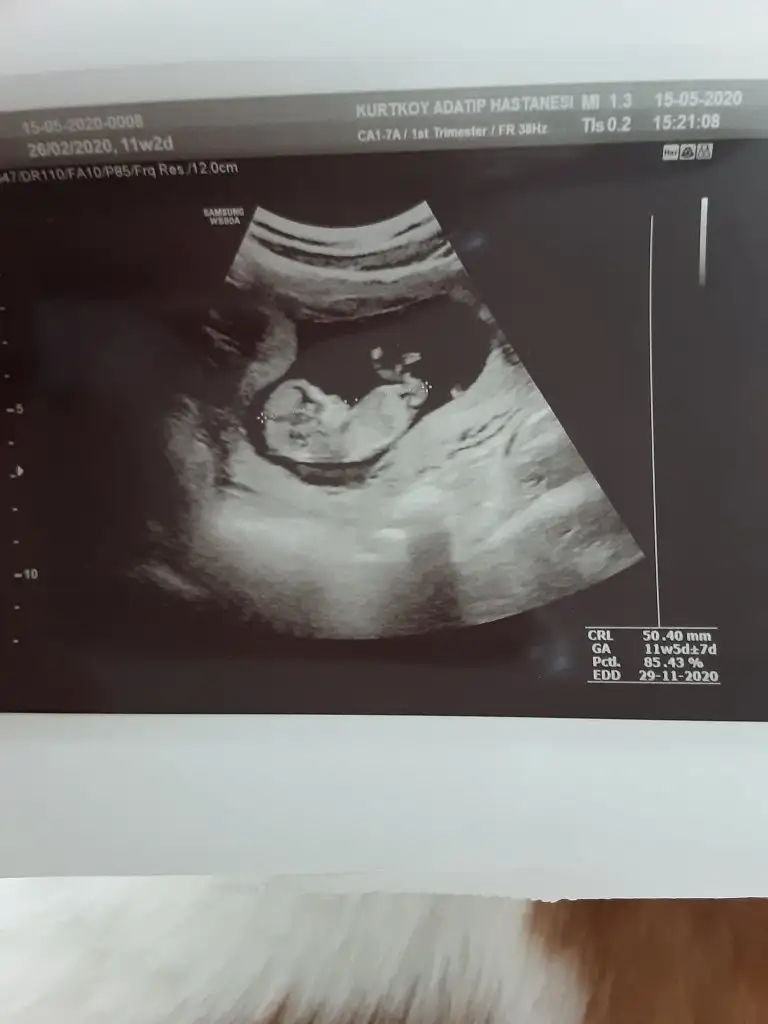

benim bebegime de bakabilir misiniz 10+6

Eklentiler

• A6F3665D-3087-415B-B58E-F7610BF63D04.webp

A6F3665D-3087-415B-B58E-F7610BF63D04.webp

31,1 KB · Görüntüleme: 63

• A02C6988-EBE0-4B69-A2DE-2B90420EA947.webp

A02C6988-EBE0-4B69-A2DE-2B90420EA947.webp

46,1 KB · Görüntüleme: 64